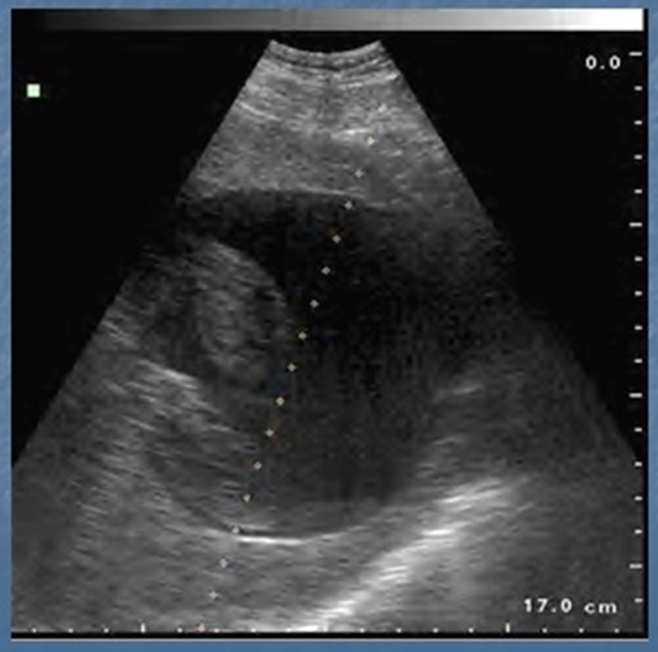

Эхинококковая киста печени СЕ3 до

дренирования

На фото представлена эхинококковая киста и

выбранная траектория первого дренажа через массивную ткань неизмененной печени: